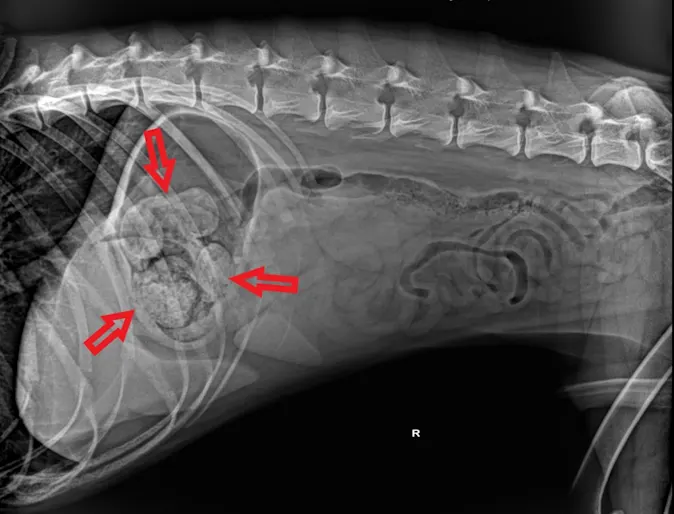

Two Mummified Fetuses in a Spayed Cat

Lena is approximately a 3 year old female, spayed, calico cat. Her new owner had brought her in within three days of adopting her, because she felt a mass in her abdomen. The mass was confirmed as abnormal on general physical exam and we decided to take an x-ray to find out more.